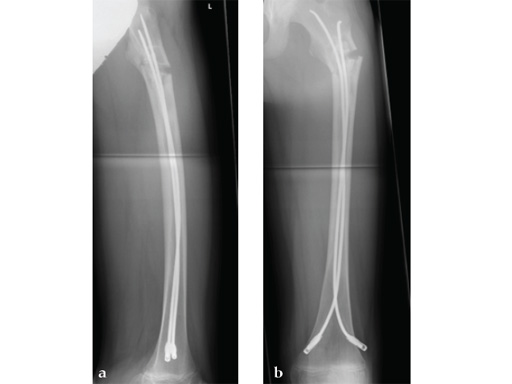

Case 1: LCP PHP 130. A 15-year-old boy sustained a refracture of a pathological fracture of the subtrochanteric region following a severe trauma, previously fixed with ESIN , diagnosis: juvenile bone cyst.

Case provided by Theddy Slongo, Bern, Switzerland